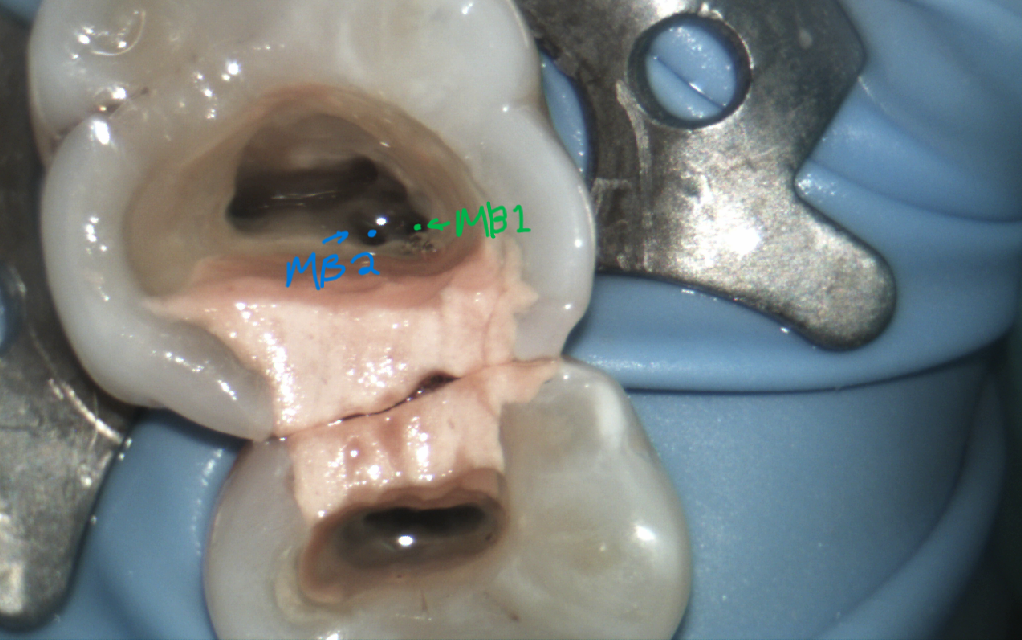

MB1 and MB2 orifices being very close together, almost confluent. These orifices lead to two seperate canals with two seperate portals of exit.